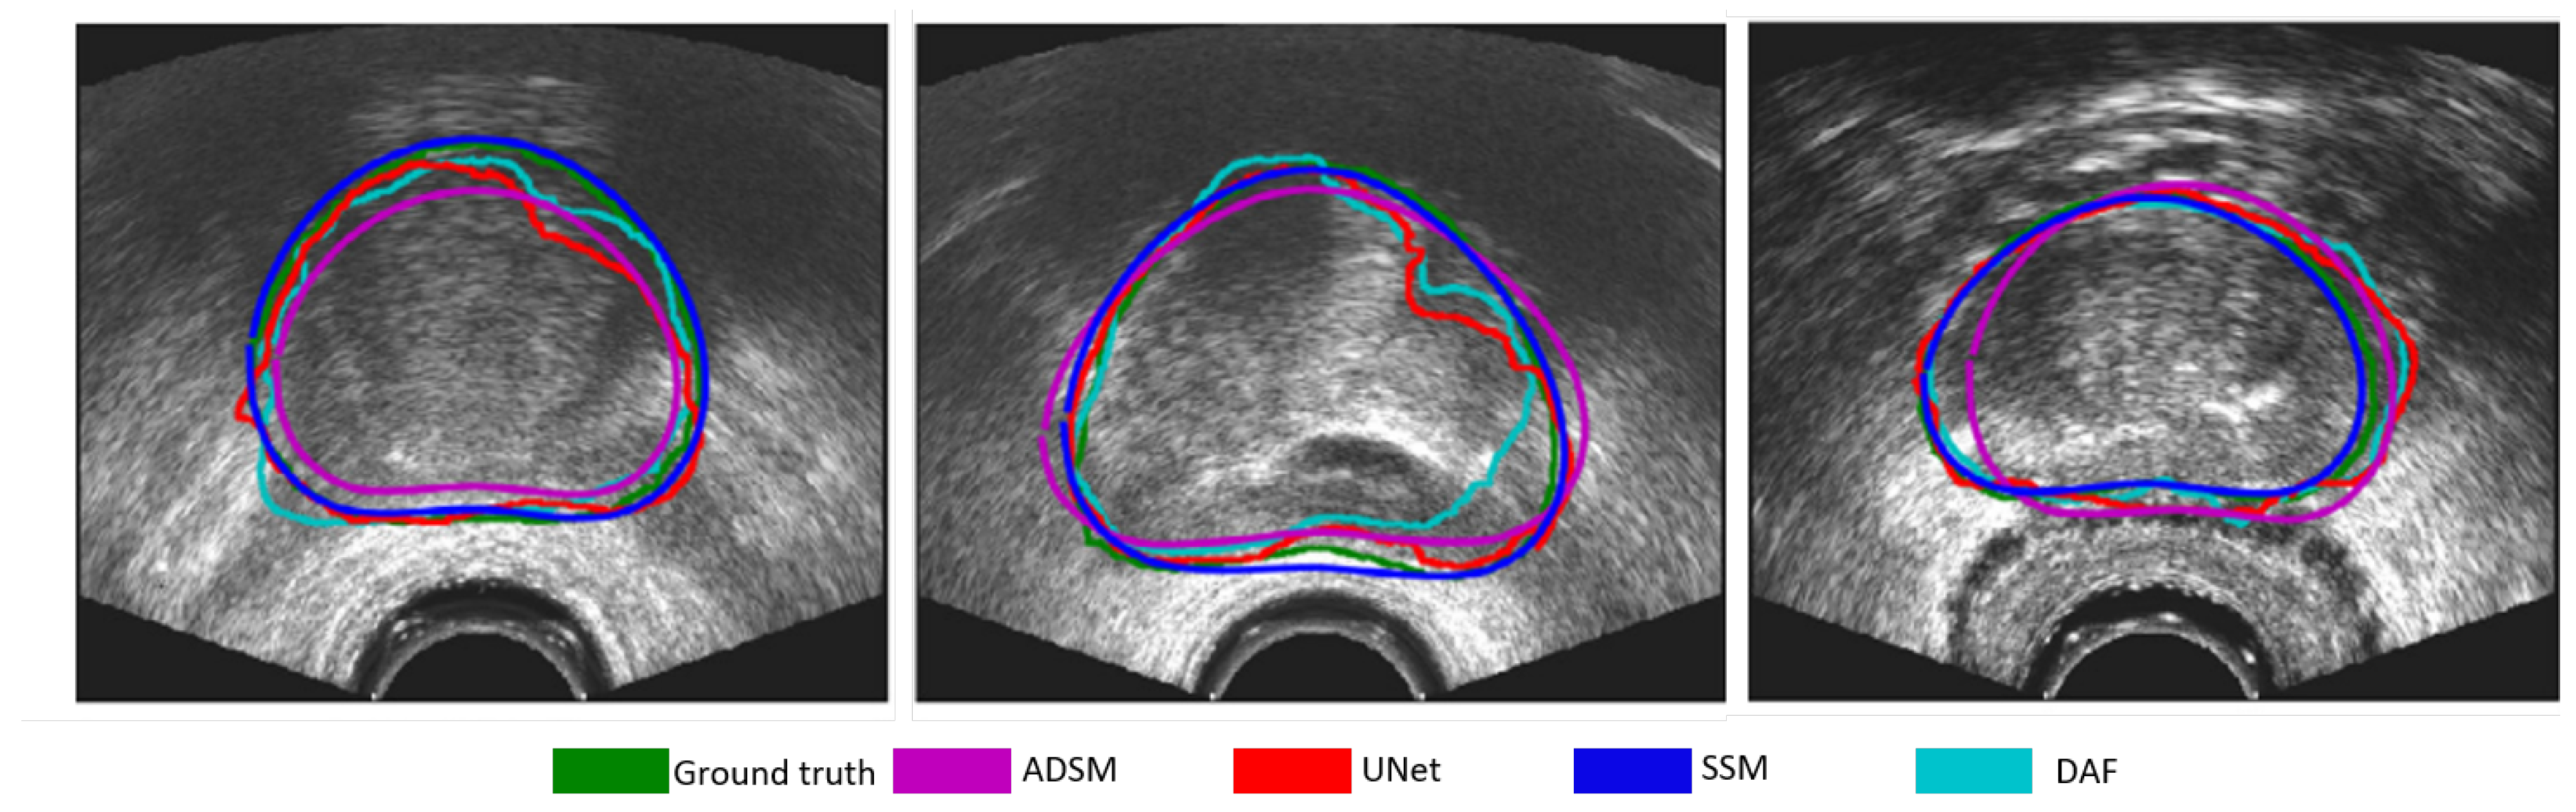

Figure 5 demonstrates some examples of prostate segmentation using different models.

Figure 5. Example prostate segmentation results by different methods, ADSM by Yan et al. [41], UNet by Ronnerberger et al. [42], SSM by Karimi et al. [16] and DAF by Wang et al. [37]. Adapted from Karimi et al. (2019) [16], with permission from Elsevier.